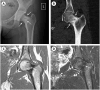

(A) Anteroposterior view of the initially obtained X-ray of the left hip evident-ly displays a radiolucent line (arrows) completely traversing the femoral neck. (B) Cor-onal reconstruction of a computer tomography (CT) scan also demonstrates the fracture line crossing the neck of the left femur in its entirety (complete fracture) (arrows). Also note the sclerotic appearance of the bone surrounding the fracture line as evidence of its chronicity (dashed oval). The findings were consistent with a complete, nondisplaced subcapital fracture (Garden type II). (C) Coronal T1-weighted non-fat-saturated MRI images and (D) coronal T2-weighted fat-saturated MRI images display a low signal in-tensity line in the left femoral neck, indicative of a fracture (arrow). Diffuse low-signal intensity changes surrounding the fracture are suggestive of adjacent sclerosis (dashed oval). The absence of increased signal intensity changes (in the T2-weighted fat-saturated MRI images) in the bone marrow surrounding the fracture indicates that this fracture has not occurred recently.